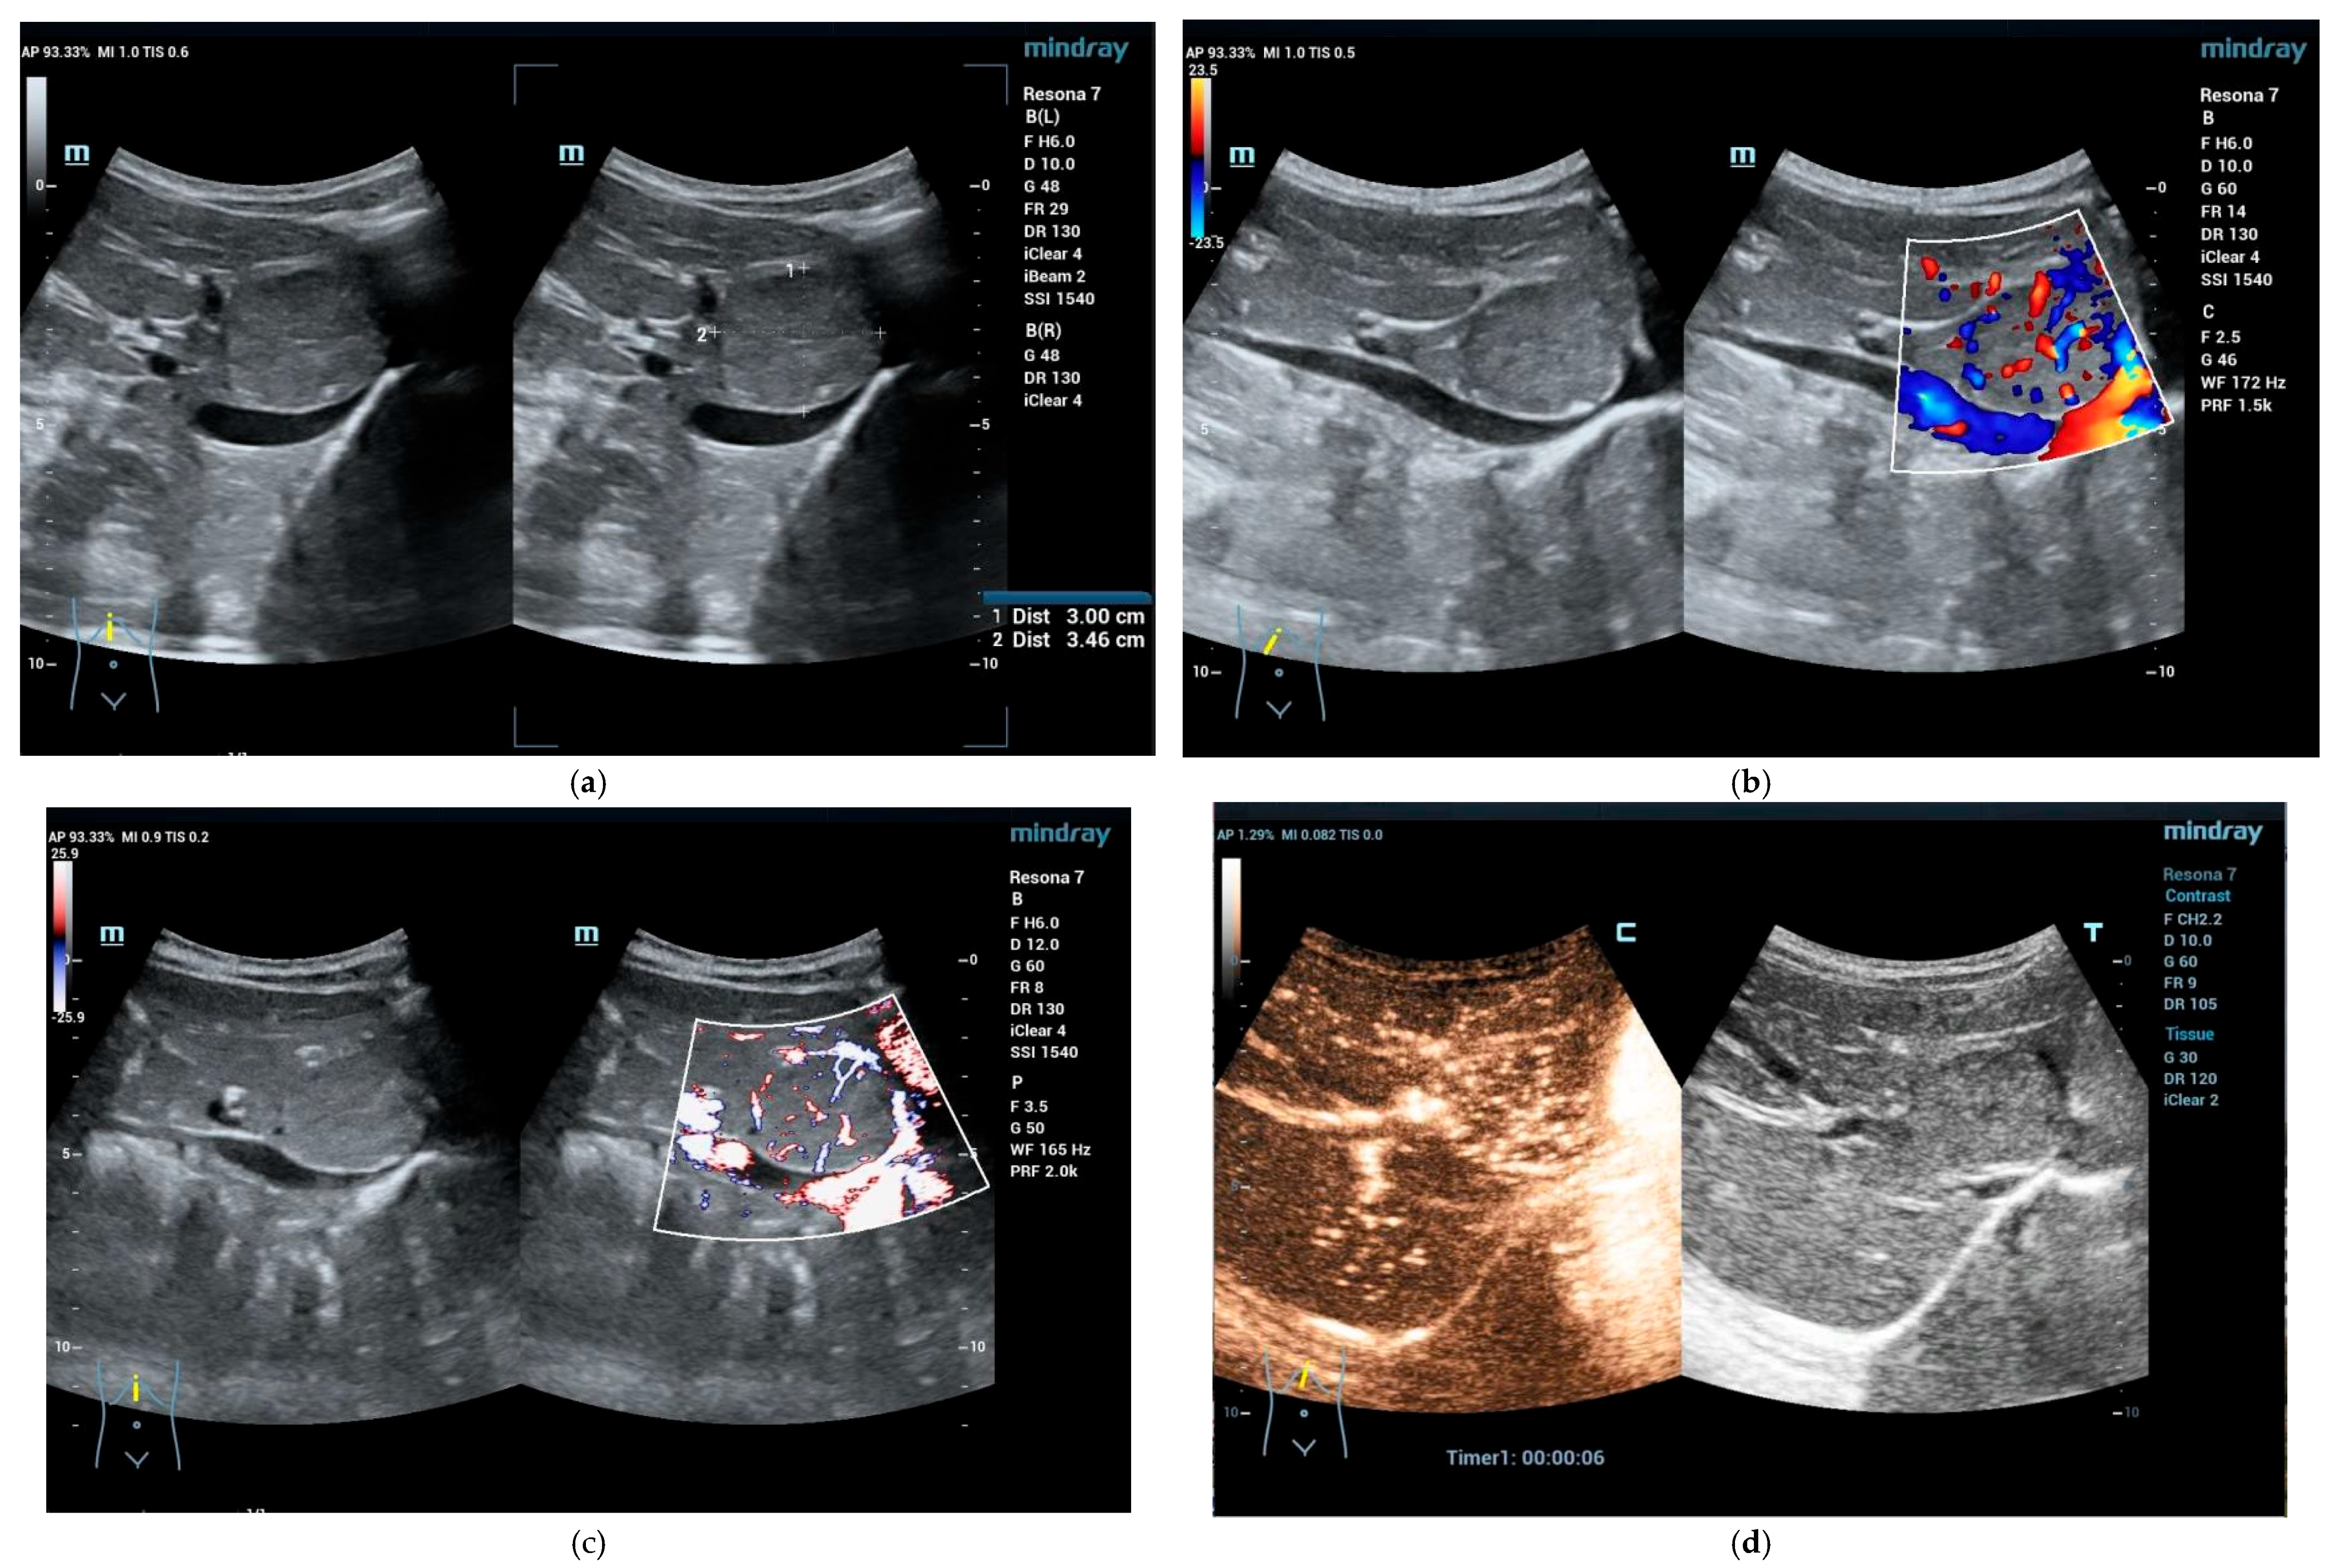

4.3.1. Hepatic Hemangioma

4.3.2. Congenital Hepatic Hemangioma

4.3.3. Infantile Hepatic Hemangioma

- Xu, M.; Pan, F.S.; Wang, W.; Zhang, X.E.; Li, X.J.; Hong, Y.; Zhou, L.Y.; Xie, X.Y.; Lyu, M.D. The value of clinical and ultrasound features for the diagnosis of infantile hepatic hemangioma: Comparison with contrast-enhanced CT/MRI. Clin. Imaging 2018, 51, 311–317. [Google Scholar] [CrossRef]

- Piorkowska, M.A.; Dezman, R.; Sellars, M.E.; Deganello, A.; Sidhu, P.S. Characterization of a hepatic haemangioma with contrast-enhanced ultrasound in an infant. Ultrasound 2018, 26, 178–181. [Google Scholar] [CrossRef]

- El-Ali, A.M.; McCormick, A.; Thakrar, D.; Yilmaz, S.; Malek, M.M.; Squires, J.H. Contrast-Enhanced Ultrasound of Congenital and Infantile Hemangiomas: Preliminary Results from a Case Series. AJR Am. J. Roentgenol. 2020, 214, 658–664. [Google Scholar] [CrossRef] [PubMed]